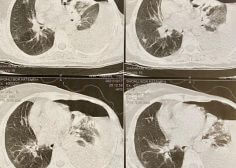

Left pulmonary malignancy and occlusion effect on LPA

Patient with left pulmonary malignancy and occlusion effect on LPA with low LVEF undergone tumor resection and PPM insertion.